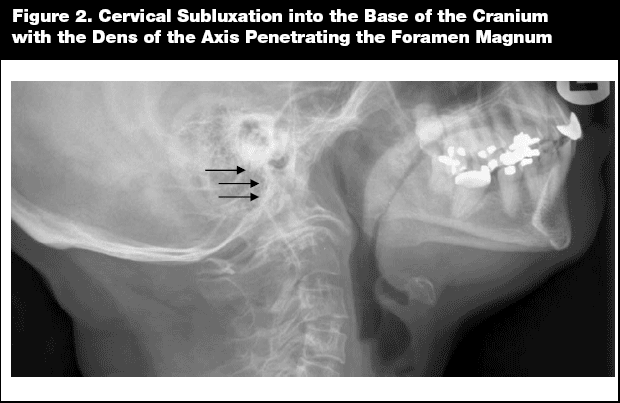

One of the earliest radiographic findings of patients with RA is the soft-tissue swelling of synovial inflammation, which transitions later to marginal joint erosions with periarticular osteopenia and joint space narrowing (as a result of cartilage loss). Radiographic findings tend to be symmetrical. Joint space narrowing typically occurs in joints like the metacarpophalangeal, the proximal interphalangeal, radiocarpal, and intercarpal joints. (See Figure 1.) The earliest signs of erosive disease often occur in the MTP joints of the feet. As opposed to the superior joint space narrowing of osteoarthritis, there may be axial or medial narrowing of the hip joints in RA. A hallmark of the synovial inflammatory changes of RA is joint space narrowing with the absence of osteophytes, which are typically present in osteoarthritis.

Later x-ray findings include mal-alignment of joints, including the classical ulnar deviation of the hands and fibular deviation of the toes, as well as the destruction and fusion of the carpal bones. The damage to the supporting ligaments of the fingers can lead to the classic swan-neck and boutonniere deformities that characterize advanced RA.